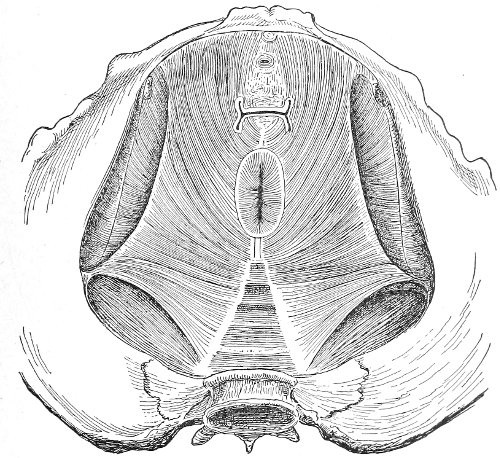

An accurate knowledge of the anatomy and mechanism of the female perineum is essential to an understanding of the nature and treatment of injuries to this structure. The anatomical structures lying between the anus behind and the symphysis pubis in front are those that most directly interest the gynecologist. Proceeding from 57 below upward, we find the following structures lying in superimposed planes: the skin, the superficial fascia, the deep layer of the superficial fascia, the transversus perinæi and the sphincter vaginæ muscles, the anterior layer of the triangular ligament, the posterior layer of the triangular ligament, the levator ani muscle (Fig. 19).

Fig. 18, A.—Superficial structures of the female perineum (Weisse).

Fig. 19.—Dissection of female perineum: on the left side the perineal muscles are exposed by the reflection of the perineal fascia; on the right side the muscles and the superficial layer of the triangular ligament have been removed, thereby exposing the deep layer of the ligament. S. V., Sphincter vaginæ muscle.

The vagina passes through these structures. They surround and support the ostium vaginæ as the fascia and muscles surround and support the opening of the rectum or the anus. The muscles and fasciæ are attached in the median line between the anus and the vagina, and therefore this part of the body, which is called the perineum, is supported or maintained in its 58 proper position by these various structures. The transversus perinæi arises from the ramus of the ischium and is inserted in the perineum. The bulbo-cavernosus, or sphincter vaginæ, arises in the perineum and is inserted in and about the clitoris. The inner fibers of the levator ani arise from the symphysis pubis and are inserted in the perineum and the lower part of the vagina (Fig. 20). When these muscles contract, their action, therefore, is to draw the perineum upward and forward. At the same time the anus is drawn upward and forward, and so also is the posterior margin of the ostium vaginæ and the lower portion of the posterior vaginal wall.

Fig. 20.—Dissection of female perineum, showing the deeper structures after removal of the levator and sphincter ani muscles.

The vagina has no circular sphincter like the anus, but 59 the vaginal month is kept closed by the action of the transversus perinæi, sphincter vaginæ, and levator ani muscles, which draw the perineum forward, and thus keep the posterior vaginal wall in apposition with the anterior wall.

Fig. 21.—Muscular floor of the pelvis seen from above.

This sling of muscles and fascia, which surrounds and supports the opening of the vagina, may readily be felt in the nulliparous woman by introducing the finger in the vagina and pressing backward and outward toward the ischio-rectal fossa. We then feel plainly, immediately within the ostium vaginæ, a firm resisting band of tissue, apparently about half an inch broad, embracing the posterior portion of the lower vagina. This band is formed by the inner edges of the various muscles and planes of fascia that have been described.

Fig. 22.—Sagittal section showing relations of the several layers of fascia within the pelvic floor (Dickinson).

The vagina extends, as a transverse slit in the pelvic floor, upward and backward, approximately in the direction 60 of a line drawn from the ostium vaginæ to the fifth sacral vertebra. It is approximately parallel with the conjugate of the brim, so that when the woman is erect the long axis of the vagina is inclined at an angle of 60° to the horizon. The vagina is not a vertical open tube: it is a slit in the pelvic floor, in health always closed by the accurate apposition of the anterior and posterior walls (Fig. 21). The anterior vaginal wall is about 2½ inches long in a vertical mesial line. The posterior vaginal wall is about 3½ inches long. The vaginal walls are triangular in shape, being broader above than below. The shape of the normal vagina at the pelvic outlet is shown by Fig. 23. The section here shows the vaginal 61 slit of the shape of the letter H. The portions of the slit extending backward and somewhat outward are called the vaginal sulci or furrows. They are directions of diminished resistance in which tears are liable to occur.

Fig. 23.—Section illustrating the characteristic form of the vaginal cleft (Henle): Ua, urethra; Va, vagina; L, levator ani; R, rectum.] 62